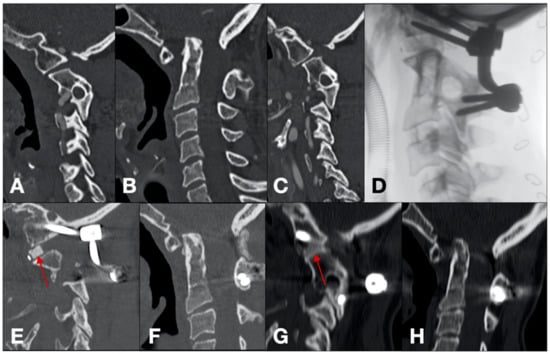

- Case 8 (Figure 4)